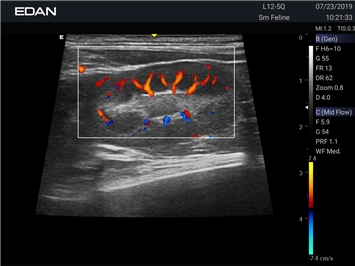

Ветеринарный ультразвук одним нажатием. Система Acclarix AX2 VET разработана с целью обеспечить бескомпромиссную производительность по доступной цене. Наличие уникальных двойных аккумуляторов в легком корпусе массой 4,5 кг из магниевого сплава позволяет системе Acclarix AX2 VET удовлетворять все потребности ветеринарных исследований, сохранив низкую стоимость.

EDAN Acclarix AX2 VET представляет собой специализированную ветеринарную ультразвуковую систему, сочетающую высокую производительность с доступной ценой. Благодаря продуманной конструкции и передовым технологиям, система обеспечивает качественную диагностику животных различных видов.

Энергетический допплер:

Цветовой допплер: